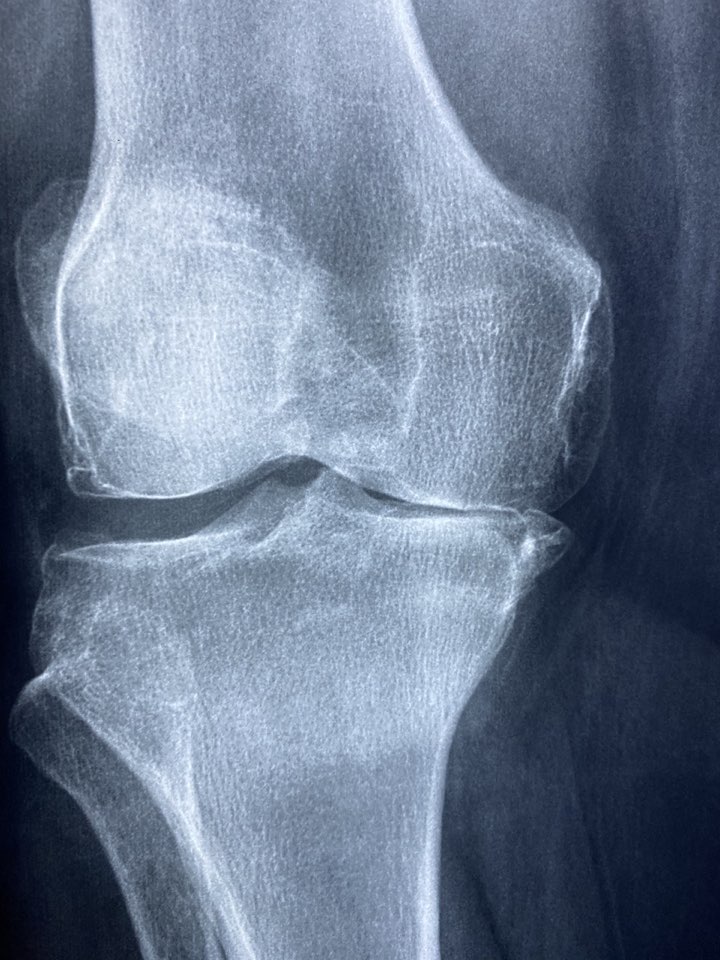

무릎 관절의 보호 연골이 부서지기 시작하면서 통증은 시작됩니다.

원래는 연골이 뼈의 끝부분을 완충시켜 부드럽고 통증 없는 움직임을 가능하게 합니다. 하지만 이 부분이 악화되면 뼈가 서로 마찰되어 통증, 염증, 뻣뻣함을 유발하여 통증을 유발하게 됩니다.

60~70대 이상은 관절의 오랜 사용으로 연골이 마모되어 무릎 통증이 나타나는 분들이 많습니다.